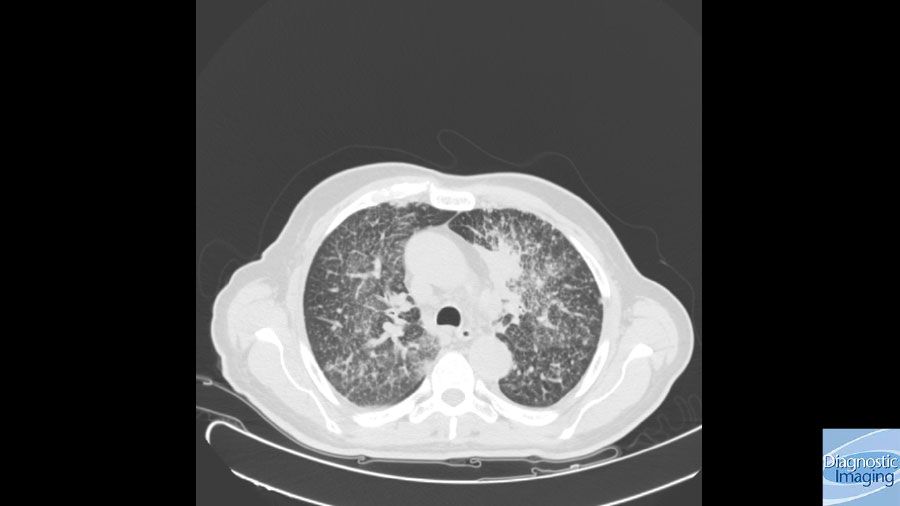

Case History: 45-year-old patient with laryngeal cancer presented with history of breathlessness, hemoptysis, increased creatinine.